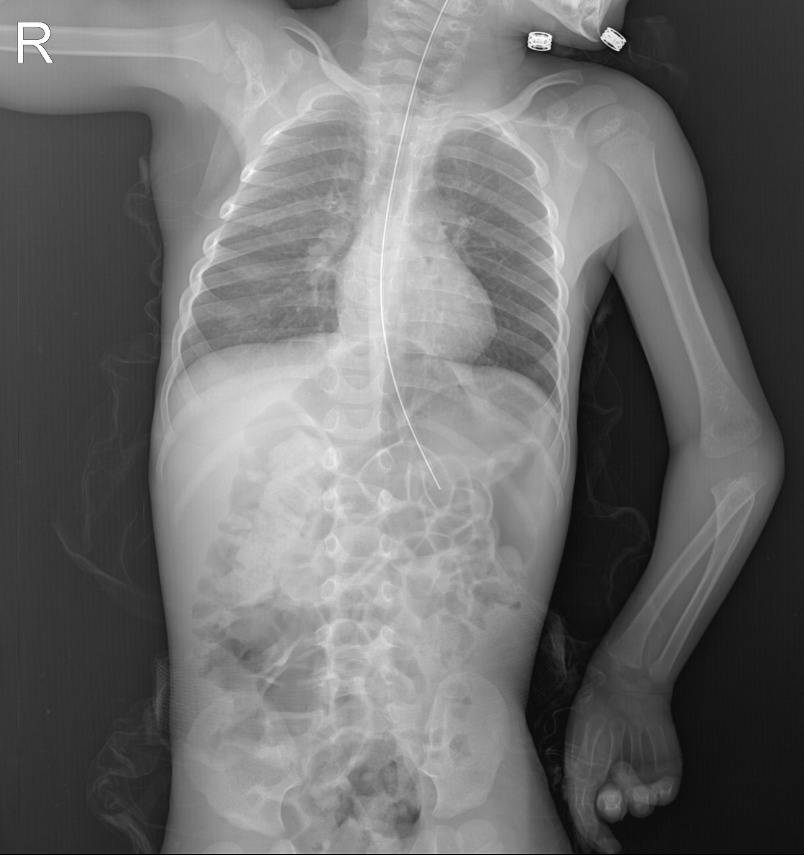

- زۆرۈر تېپىلغاندا رېنتگېن نۇرى ئارقىلىق نەيچىنىڭ ئورنى جەزملەشتۈرۈلىدۇ.

نەيچە تاقاش جەريانى تېببىي خادىملار تەرىپىدىن ئىنتايىن ئەستايىدىللىق بىلەن ئېلىپ بېرىلىدۇ. ئالدى بىلەن بوۋاقنىڭ بۇرنىدىن قۇلىقىغىچە، ئاندىن قۇلىقىدىن كۆكرەك ئاستىدىكى ئاشقازان ئورنىغىچە بولغان ئارىلىق ئۆلچىنىدۇ. نەيچە كىرگۈزۈلگەندىن كېيىن، ئۇنىڭ توغرا ئورۇنغا بارغان-بارمىغانلىقىنى جەزملەشتۈرۈش ئۈچۈن تۆۋەندىكى تەكشۈرۈشلەر ئېلىپ بېرىلىدۇ:

- نەيچە ئارقىلىق ئازراق ئاشقازان سۇيۇقلۇقى شوراپ چىقىرىلىپ، pH قەغىزى بىلەن كىسلاتالىق دەرىجىسى تەكشۈرۈلىدۇ.

- ستەتوسكوپ (ئاڭلاش ئەسۋابى) ئارقىلىق ئاشقازانغا ھاۋا كىرگۈزۈپ، ئاشقازاندىكى تاۋۇش ئاڭلىنىدۇ.